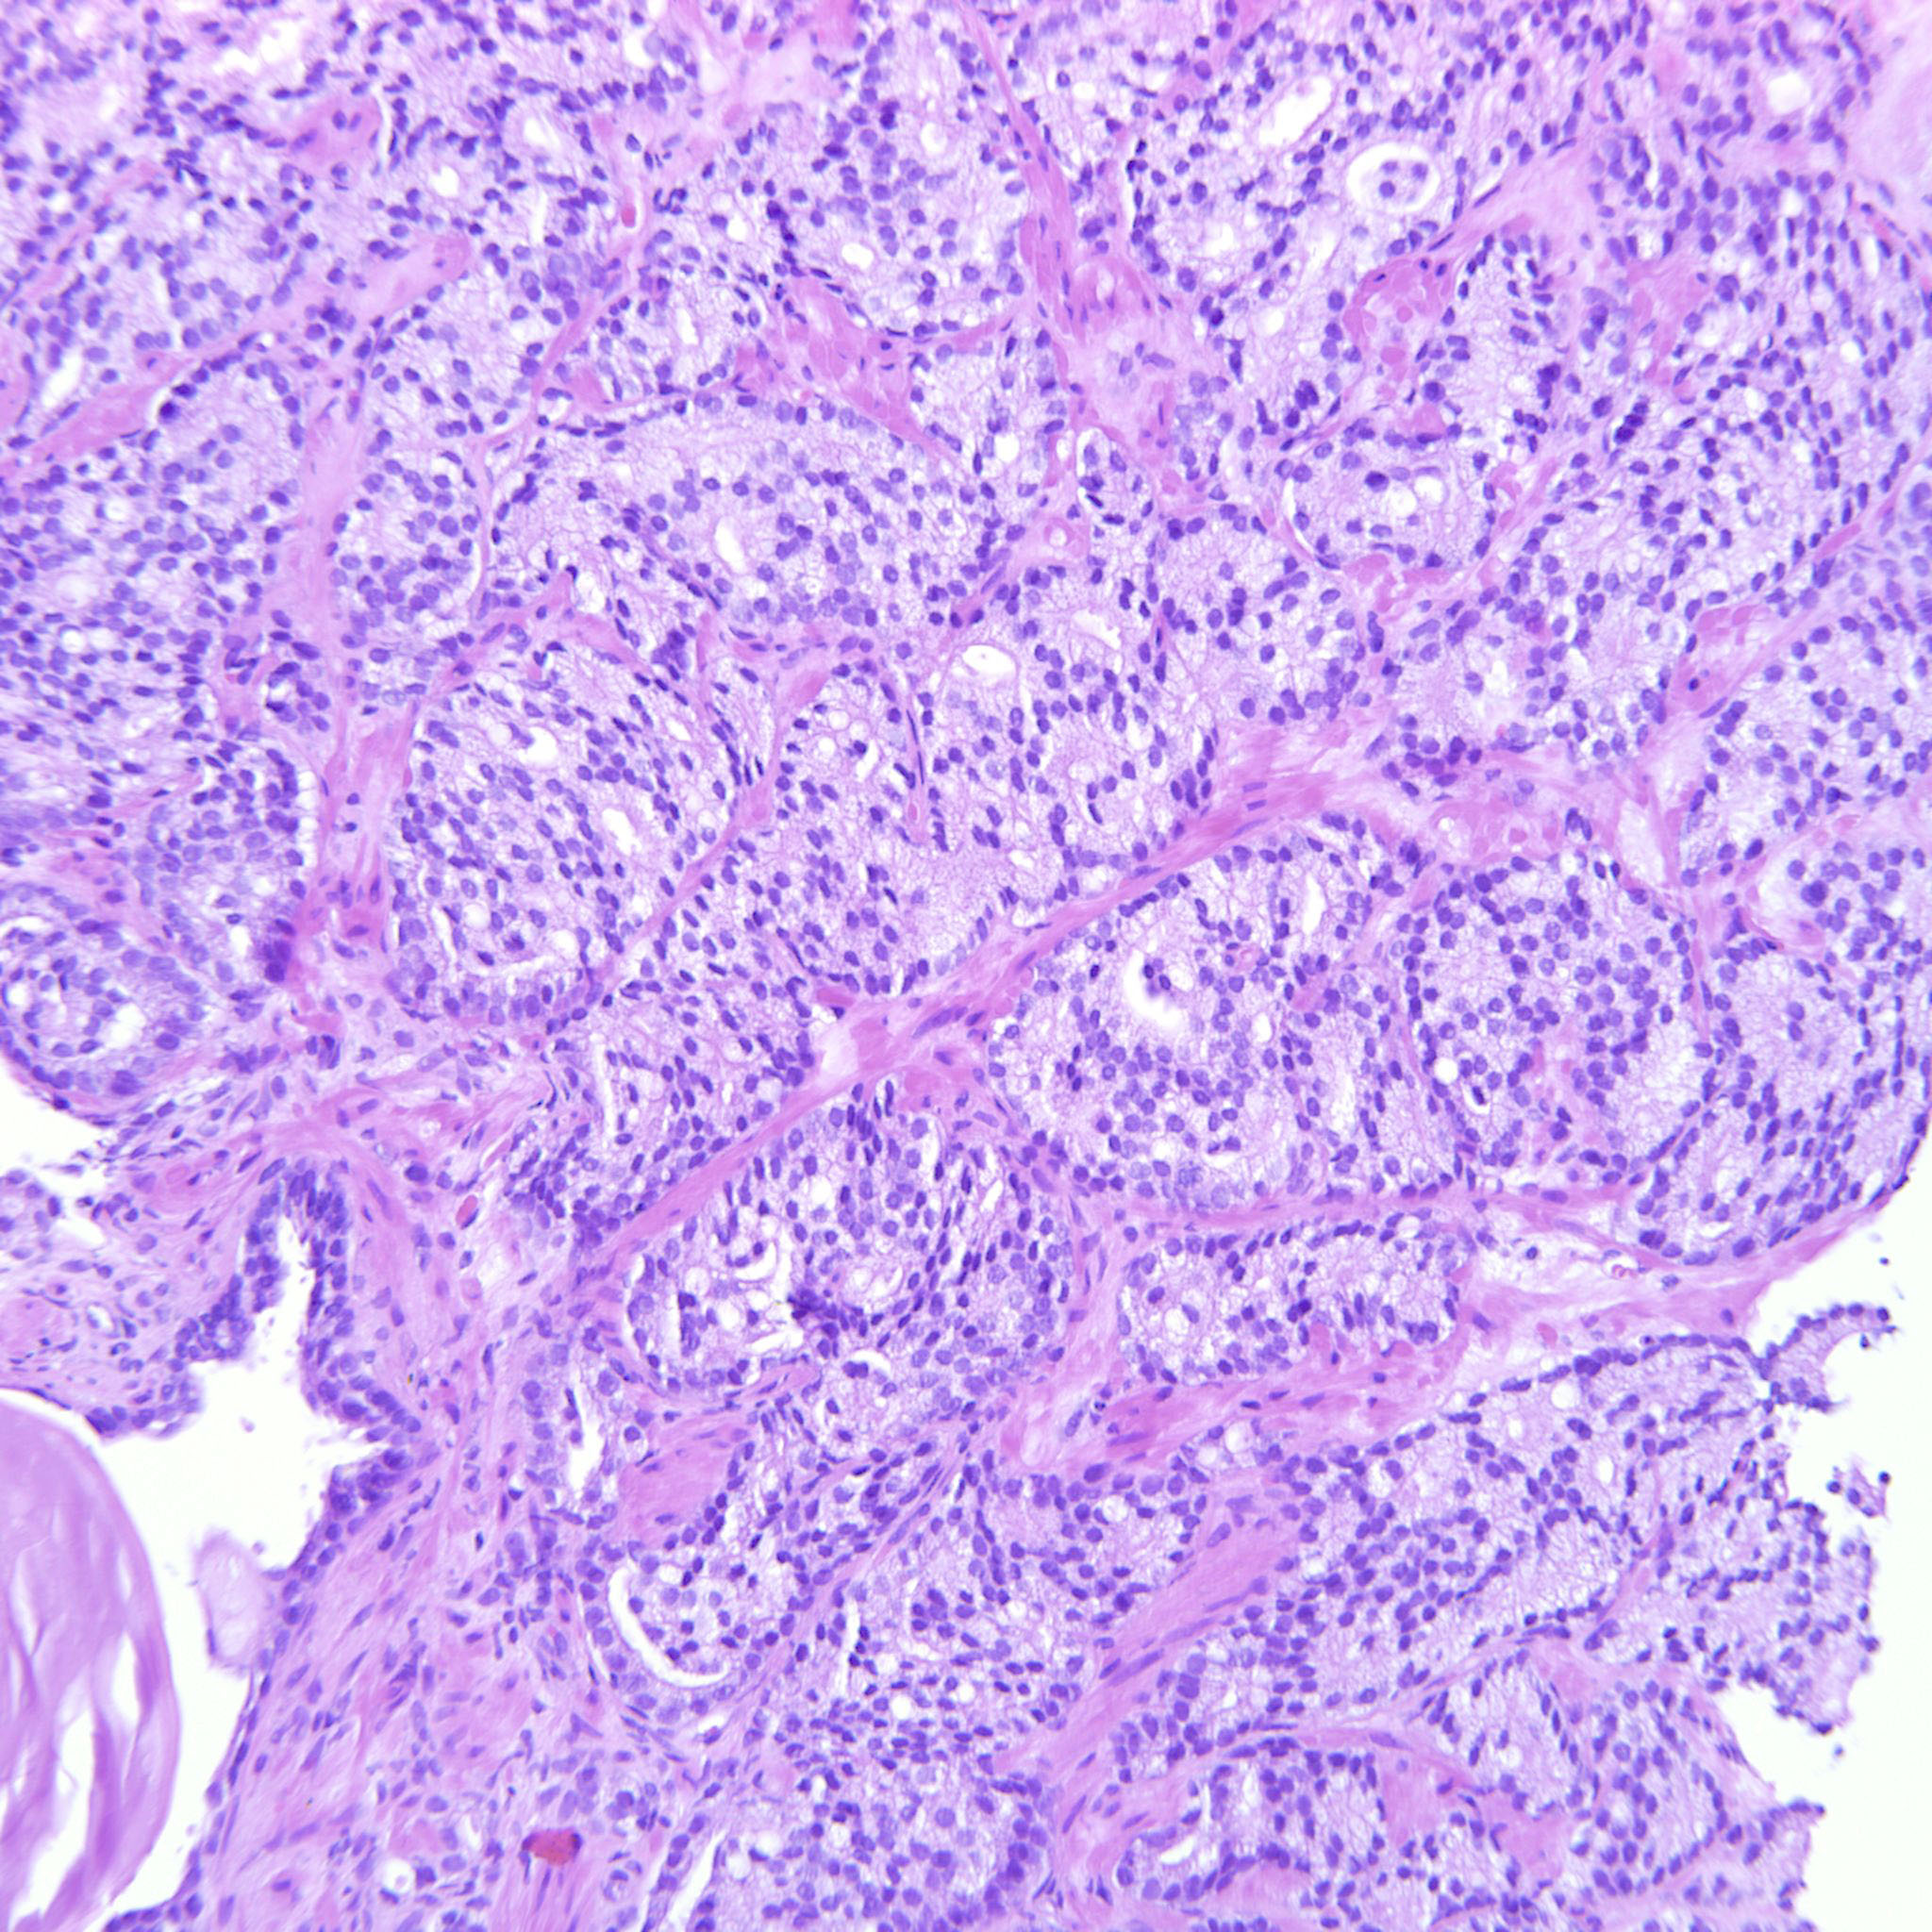

Prostate cancer grading

Case ID: 122